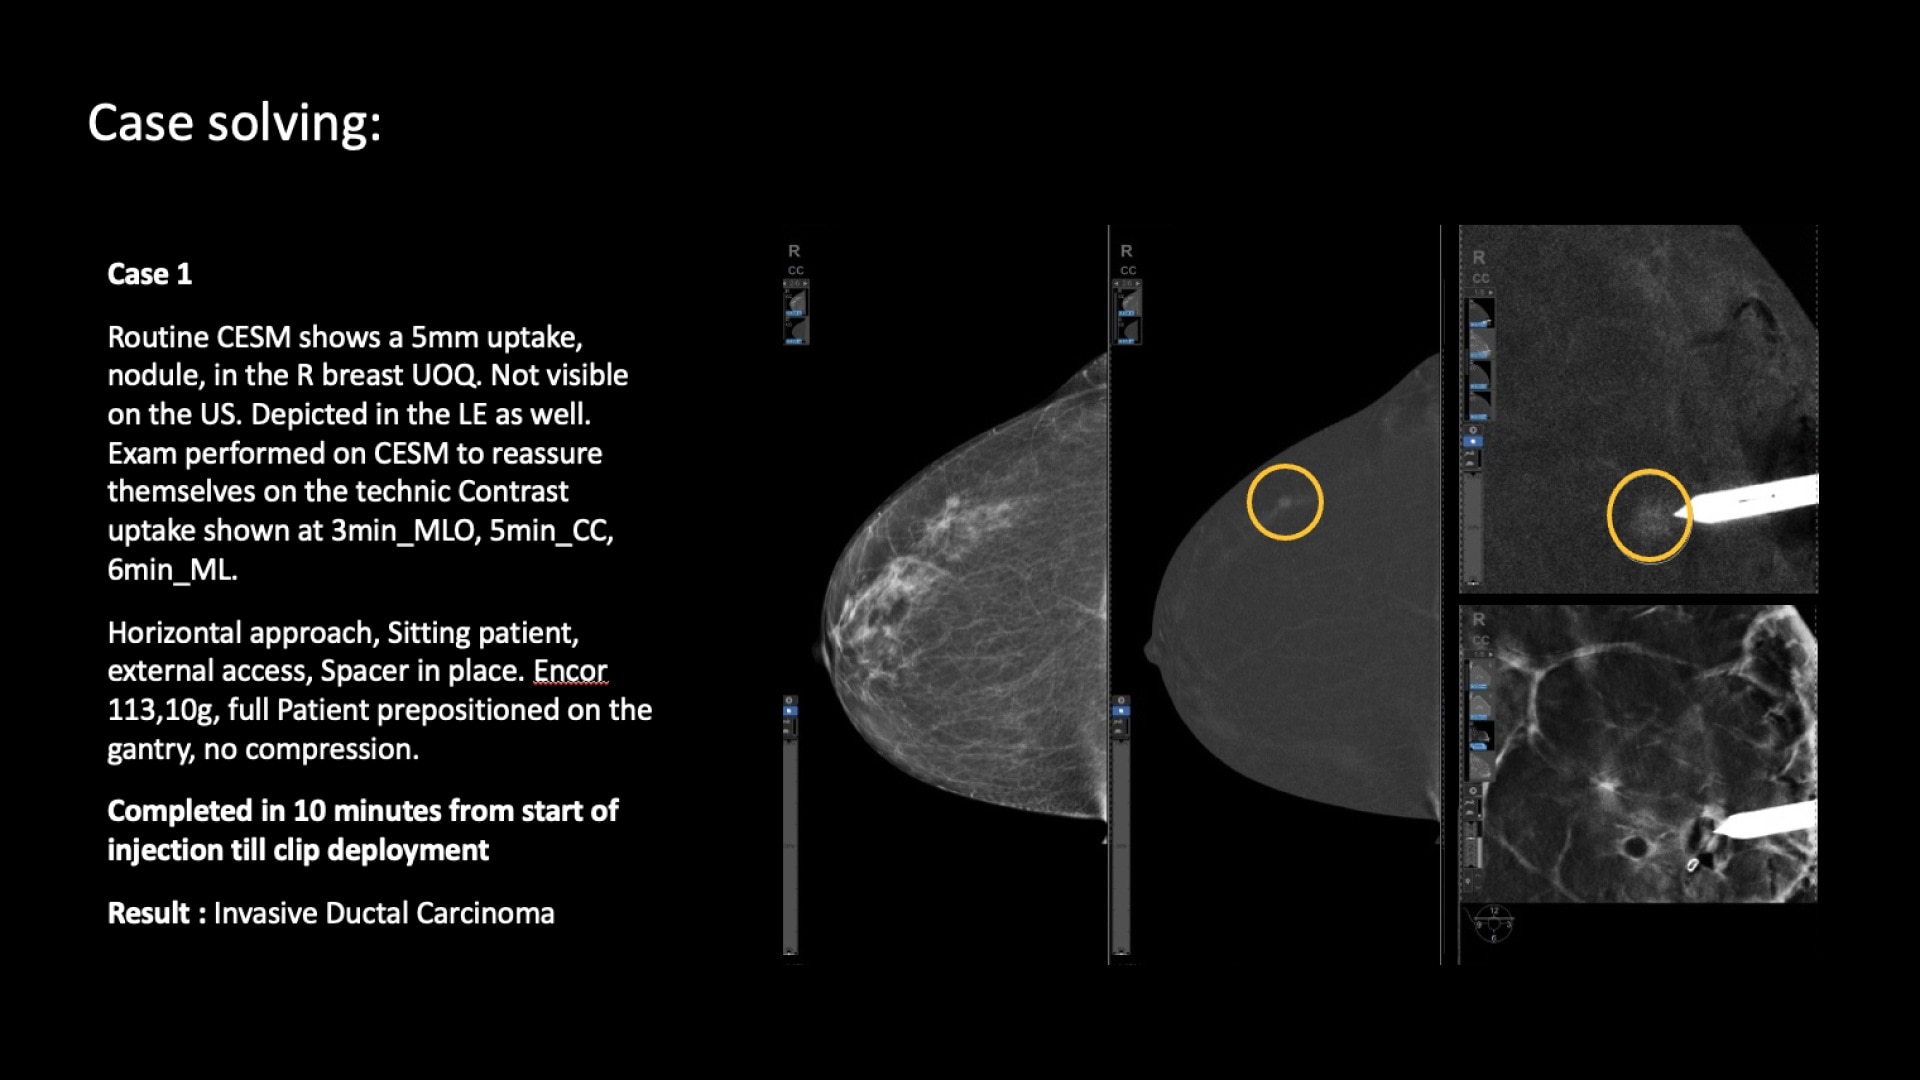

SEE AND BIOPSY WHAT MATTERS

Serena Bright™

Contrast-guided biopsy solution

Utilizes contrast-spectral mammography to clearly target and biopsy lesions without leaving the mammography suite.